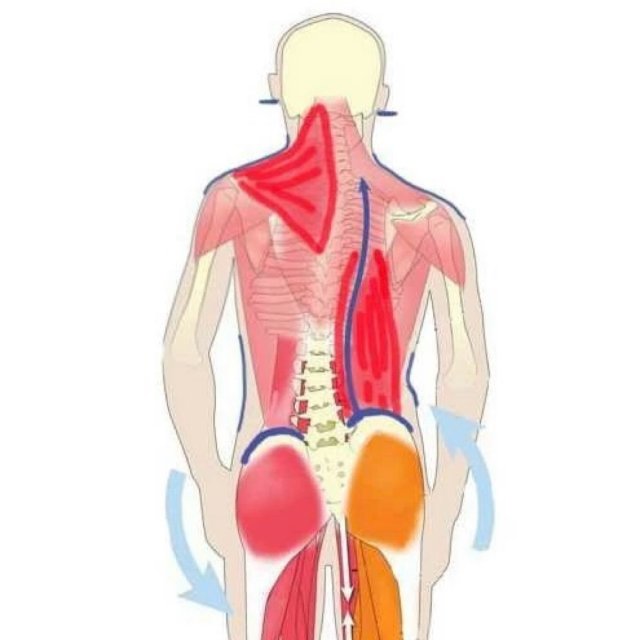

Анатомия и упражнения: Перекос таза и мышцы бедра